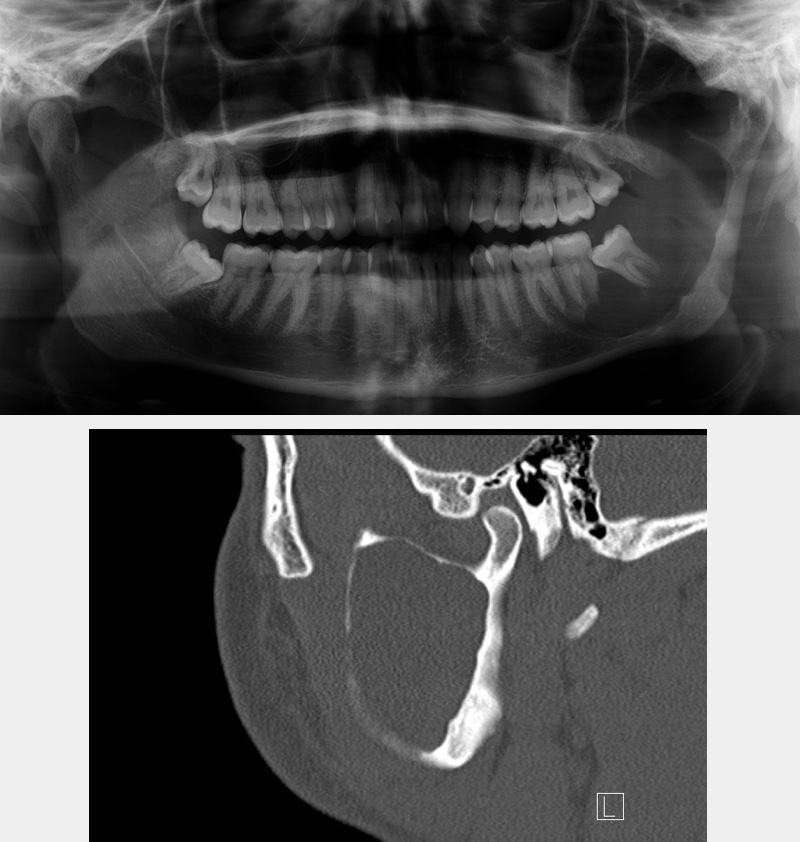

Other applications include a range of bone lesions such as cystic lesions of the jaws (Figure 11).

Figure 11: A benign cystic lesion of the mandible; comparison of a conventional two-dimensional X-ray image (DPT; top) and a CT scan (bottom).